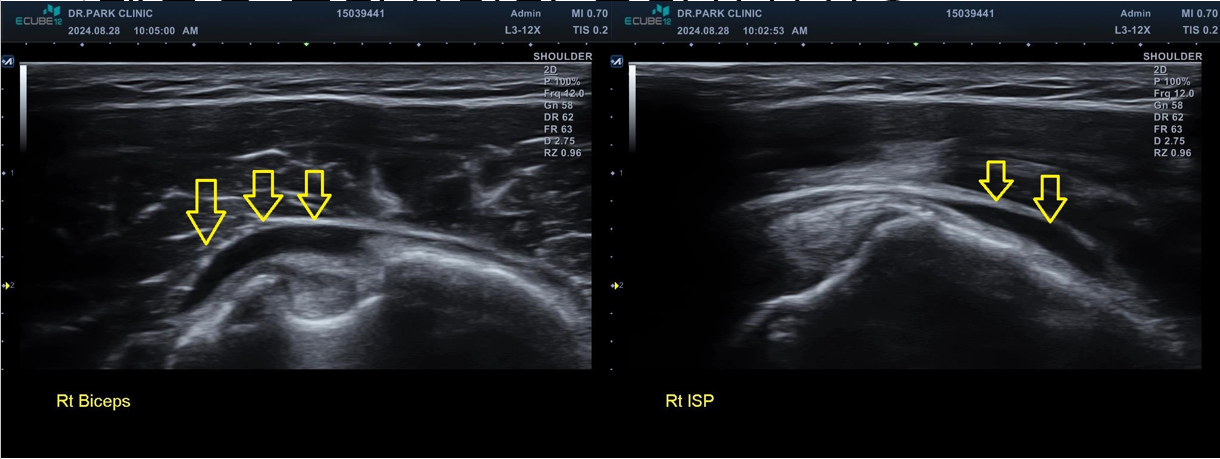

진짜 문제는 초음파 검사였는데요... 초음파 검사상에는....

우선 어깨의 윤활낭이라는 공간이 있습니다. 어깨를 사용하면서 주변 조직과 부딪힐때 이 충격을 흡수해주는 물이 담긴 공간인데요. 이 공간에 물이 차있는게 보이네요. 쉽게 말하면 염증이 심해져있는 거죠

마지막 초음파에서는 어깨 극상근의 파열 소견이 관찰되고 있습니다. 정확한건 mri 를 찍어봐야 하겠지만 찢어진 길이와 정도로 봐서는 수술이 필요한 극상근 전층파열로 생각이 됩니다.